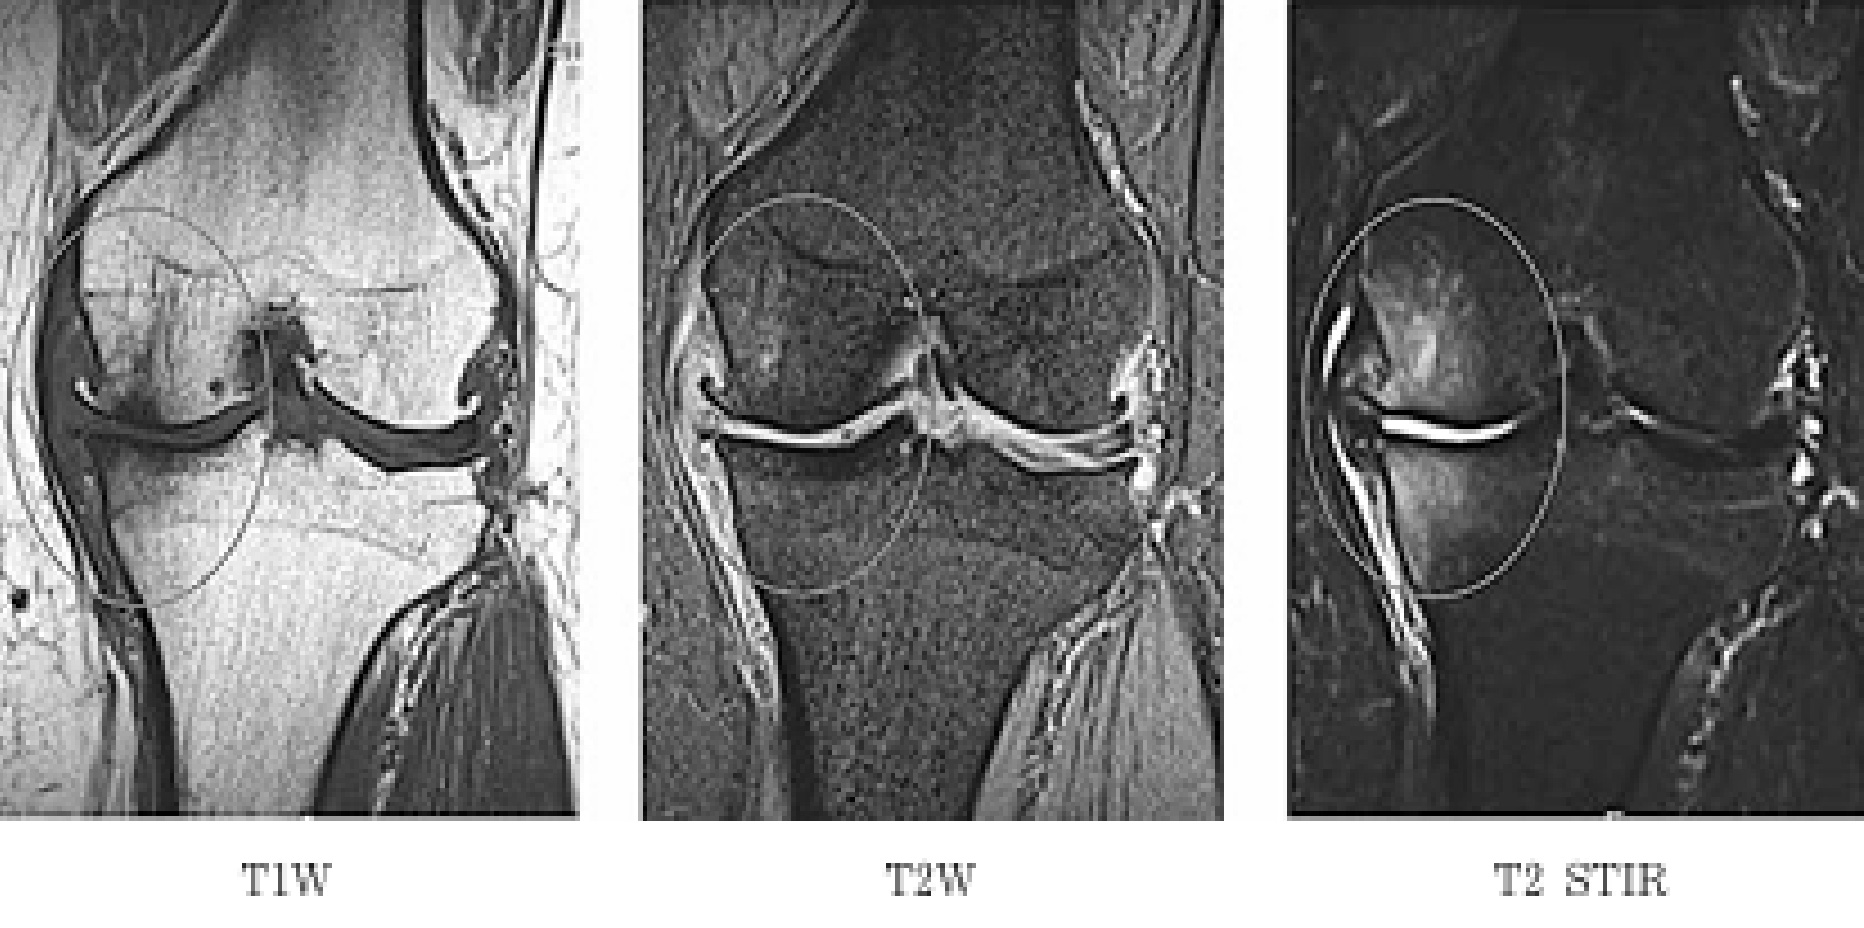

- MRI検査

- レントゲンでは分からない

・軟骨の損傷

・半月板の断裂

・骨の中のむくみ(BML:骨髄病変) などを詳しく確認します。

・半月板や骨病変はレントゲンなどでは判断できずMRIでしか確認できないため、早期の診断・受診が必要になります。

MRIで確認されるBMLや内側半月板後根断裂(MMPRT)は進行の引き金となるため早期受診が重要です。